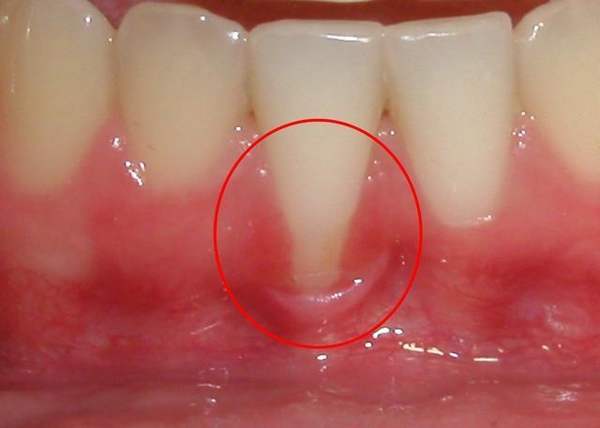

牙根暴露出來是怎么回事?

一般情況下,人的牙根會包裹在牙齦中,然而有些人卻發(fā)現(xiàn),自己的牙齒越長越長,牙根也暴露出來,遇到冷熱刺激還會痛,這是怎么回事呢?

由于牙根暴露,??砂l(fā)生牙本質(zhì)敏感癥、牙頸部齲和根面齲。牙頸部楔狀間隙增大,易發(fā)生水平型食物嵌塞,從而易產(chǎn)生炎癥,加重牙齦退縮。建議及時到口腔醫(yī)院檢查,根據(jù)病因進(jìn)行針對性治療。